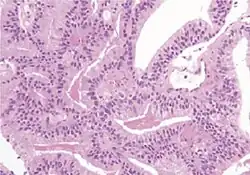

Microscopic characteristics

- Specific but relatively rare

- [notes 4]

- Collagenous micronodules[4]

- Glomerulations,[4] epithelial proliferations into one or more gland lumina, typically a cribriform tuft with a single attachment to the gland wall.[18]

- Perineural invasion.[4] It should be circumferential[18][notes 5]

- Angiolymphatic invasion[4]

- Extraprostatic extension [4]

- Less specific findings.

- Mitoses (also seen in for example high-grade prostatic intraepithelial neoplasia (HGPIN) and prostate inflammation).[4]

- Prominent nucleoli[4]

- Intraluminal eosinophilic secretion[4]

- Intraluminal blue mucin[4]